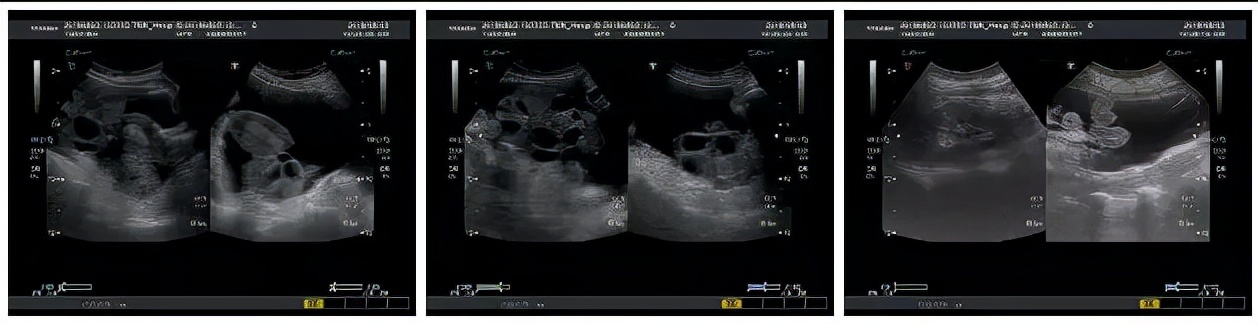

一般临床表现主要为卵巢囊性增大、毛细血管通透性增加、体液积聚于组织间隙,引起腹腔积液、胸腔积液,伴局部或全身水肿。一般可将OHSS分为轻、中、重度三种。

轻度 :表现为胃胀、食欲差、下腹不适、沉重感或轻微下腹痛。B超检查卵巢增大,直径≤5cm。

中度 :有明显下腹胀痛,可伴有恶心、呕吐、口渴,偶伴腹泻,体重增加≥3kg。B超检查卵巢增大,直径在5~10cm,腹腔积液<1.5L。

重度 :腹腔积液明显增加,尿少、恶心、呕吐、腹胀,严重者无法进食,疲乏,出冷汗,甚至虚脱。大量腹腔积液使膈肌升高或有胸腔积液时呼吸困难,不能平卧。B超检查卵巢增大,体重增加>4.5kg。